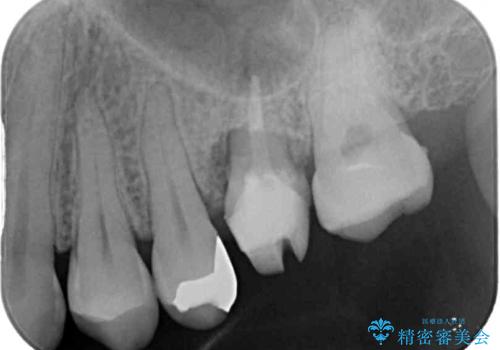

- 近医にて抜歯が必要と診断されたとのことで来院された患者様です。

術前の診査では、歯が破折している可能性が高いものの、確実に抜歯が必要と診断ができない状態でした。

状況次第では抜歯が必要となり、その際にはインプラント治療を行うことを了承いただいた上で、破折していない場合には根管治療を行うこととしました。

土台の材料を外して顕微鏡下で確認したところ、歯根にまで及ぶ破折が認められたため、インプラント治療を行うこととしました。